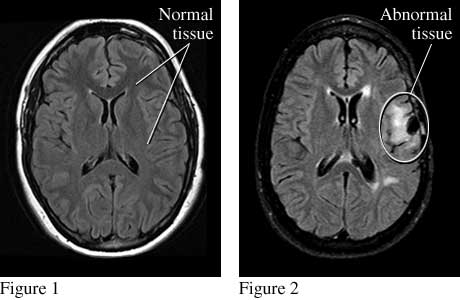

Images of normal brain tissue and abnormal brain tissue that causes seizures.

Top views of the brain show normal tissue (see figure 1) and abnormal tissue (from an injury) that causes seizures (see figure 2).